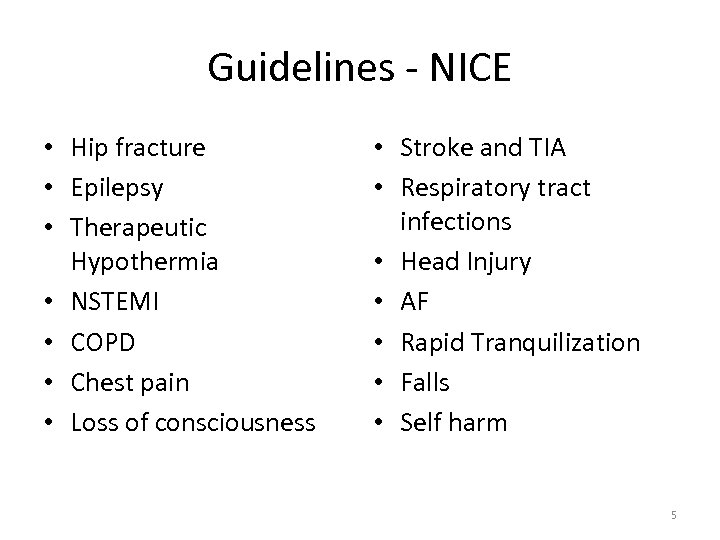

Guidelines - NICE • Hip fracture • Epilepsy • Therapeutic Hypothermia • NSTEMI • COPD • Chest pain • Loss of consciousness • Stroke and TIA • Respiratory tract infections • Head Injury • AF • Rapid Tranquilization • Falls • Self harm 5